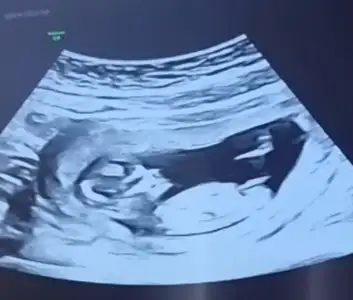

Çok net erkek .11 12 haftalık nub kız görünüyor du. Sonra yükseldi galiba. 12 +5 e kadar güven vermiyor nubYaa 11 hafta yanitti demekki çok paralel görünüyor du varmı 13 hafta bakmak isterim![]()

Kız görünüyorEki Görüntüle 2826055

Kız görünüyorIkra meyra bana 11 haftalikken kız demiştiniz. Şimdi 12 haftalik kontrolden geldim. Doktor bacak arasini da çekti ama hiç tahminde bulunmadı. Sizce hala kız mı?